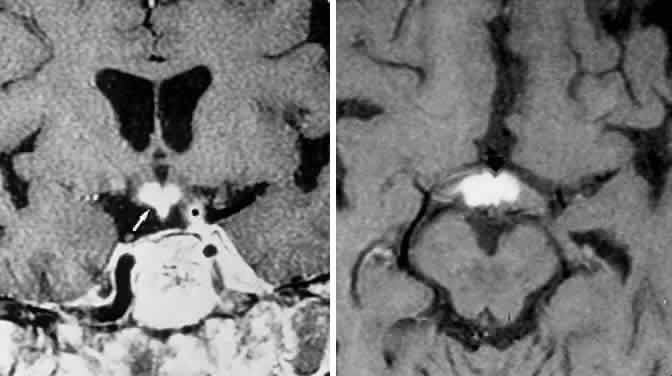

The absence of field defects, for example, in patients undergoing evaluation for amenorrhea, galactorrhea, or sellar enlargement incidentally discovered, does not imply the absence of an adenoma. Obviously, patients with microadenomas, that is, confined within the sella, do not have field defects. From a study24 of 50 cases of pituitary adenomas with chiasmal syndrome, it was concluded that visual disturbance occurs when the chiasm is displaced approximately 10 mm upward (see also Volume 2, Chapter 4, Fig. 6). The modern management of pituitary adenomas should involve several disciplines: current neuroradiologic studies detect microadenomas and provide precise delineation of gross morphology and status of neighboring structures, and mixed MRI signals suggest new or old hemorrhage, cysts, and so forth (Fig. 2); radioimmunoassay techniques assay PRL and other endocrine levels; oral neuropharmacologic agents, such as bromergocryptine, provide a “medical adenomectomy” for hyperprolactinemia and acromegaly; transsphenoidal surgery, including high-illumination microscopical procedures, televised radiofluoroscopic monitoring, and infection control, has all but replaced transcranial approaches; immunohistochemistry techniques have replaced the anachronistic tinctorial designations (e.g., chromophobe, basophilic) with a functional classification.

Fig. 2. Large prolactinoma. Original vision in the right eye (RE) was 8/200, left eye (LE) 1/200, with serum prolactin of 26,000 ng/ml and galactorrhea. Four months of bromocriptine reduced prolactin to 661 ng/ml, vision improved to RE 20/40, LE 20/50. At 3 years, vision was as follows: RE 20/30, LE 20/20; prolactin was 25.9 ng/ml. Enhanced magnetic resonance imaging. Sagittal (A) and coronal (C) images at diagnosis. Sagittal (B) and coronal (D) images at 2-year follow-up, showing dramatic shrinkage of the mass.